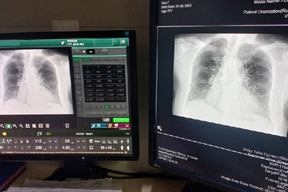

Más acceso, menos demoras. El Hospital María Auxiliadora desarrolló una jornada extraordinaria para acelerar la toma de radiografías y atender a usuarios que permanecían en programación pendiente.

La habilitación de turno dominical, en mañana y tarde, permitió descongestionar el área, maximizar el uso de equipos y reforzar la respuesta del servicio de imágenes.